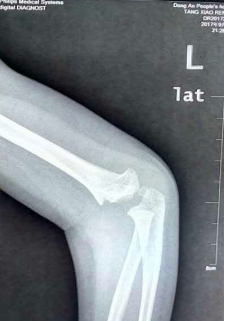

手術前X片:提示患兒肱骨髁上粉碎性骨折(伸直型),冠狀位為尺偏移位,水平面有旋轉(zhuǎn)移位,矢狀位骨折遠端向后移位。